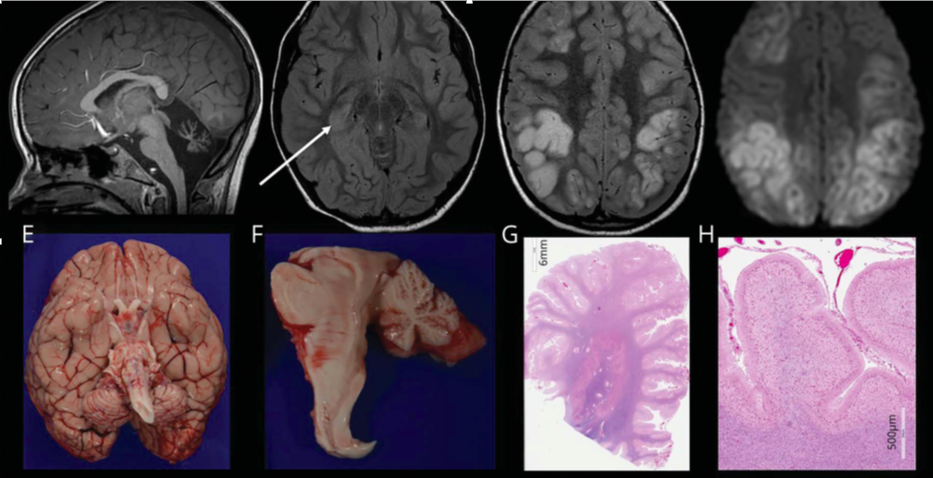

图1 严重的CACNA1A基因相关疾病的神经影像学和组织病理学特征 (A–D) 5岁时入院第2天(A,B)和第10天(C,D)的脑MRI。(A) 矢状位T1图像提示小脑蚓部萎缩;(B)轴位FLAIR图像提示右侧海马信号增强、体积增大(箭头);(C)轴位FLAIR序列提示皮质高信号;(D)轴位DWI序列提示皮质多处弥散受限,以额顶部为主(未显示相应的表观扩散系数图)。(E-H)神经病理学结果。(E)大脑大体图像显示小脑和脑干偏小;(F)脑干和小脑的中矢状切面突出了蚓部和小脑半球偏小;(G)整个小脑半球提示脑叶萎缩;(H)在高倍镜下显示小脑叶已经完全丧失浦肯野细胞和外部颗粒细胞层并伴有胶质增生。

死亡后进行脑活检和神经病理学检查(图E-H)。小脑蚓部和半球萎缩,脑干内无其他病灶。浦肯野细胞完全丧失。右侧枕叶可见累及大脑皮质的出血性病变。